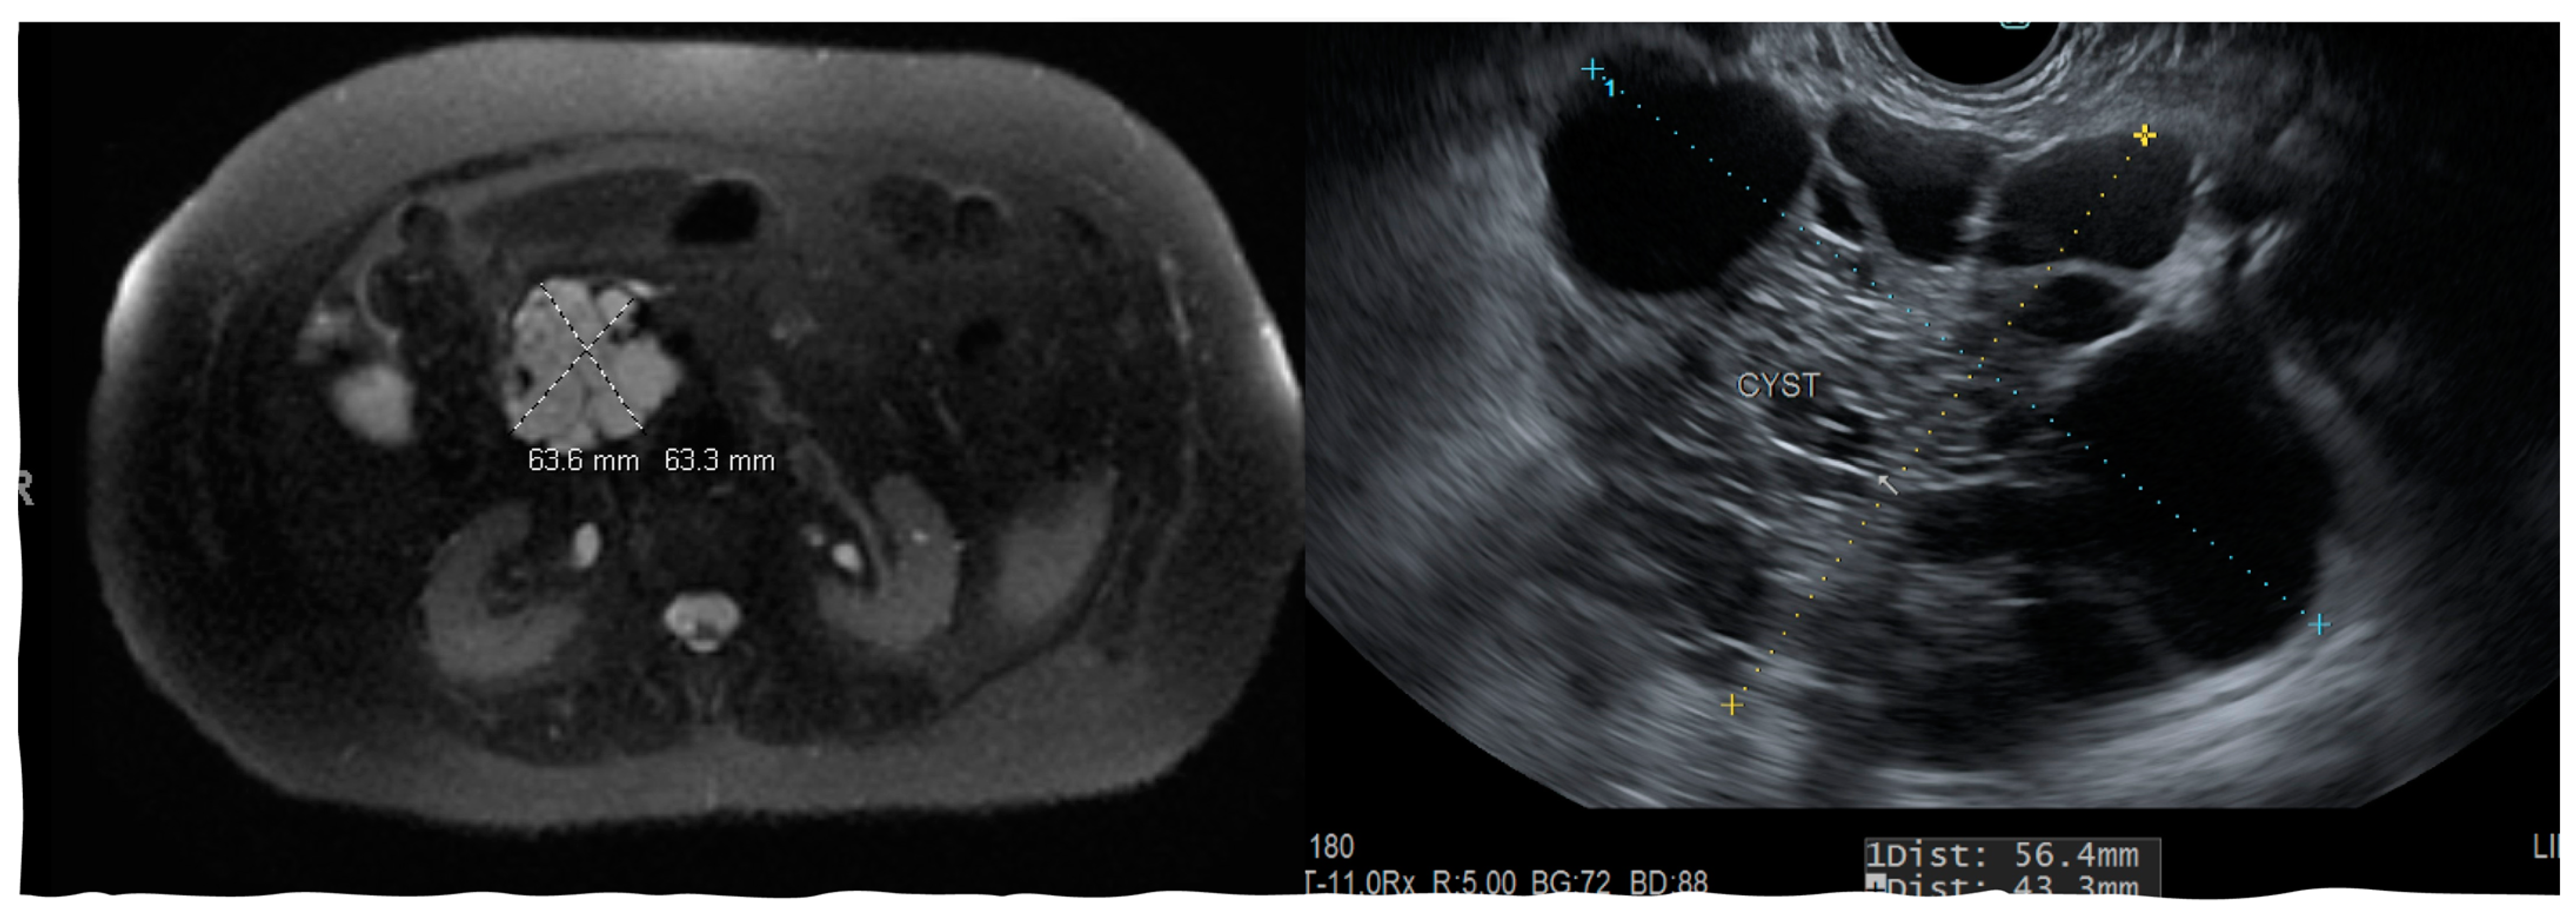

The above classifications are based on the pathologic examination of the resected PC. Imaging modalities and the analysis of PC fluid can provide a clue towards identifying cyst types; however, the degree of dysplasia and its malignant potential can still be uncertain. Most non-neoplastic pancreatic cysts are pseudocysts (Figure 1) and are seen following acute pancreatitis or are associated with chronic pancreatitis.

Figure 1.

Endoscopic ultrasound and CT scan images showing pancreatic pseudocyst near the uncinate process.